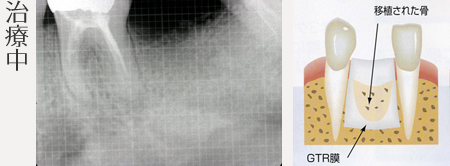

骨のない部分に膜(GTR膜)を貼り、自家骨、骨補填剤を使用して欠損部分の骨を再生します。

骨造成を行います。